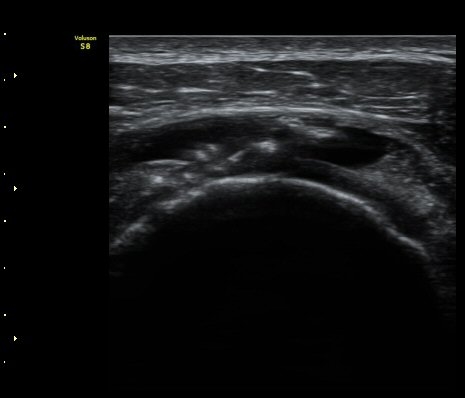

±Ø»ó°Ç Á¾´Ü¸é°Ë»ç¿¡¼­ ±Ø»ó°ÇÀÇ ÀüÃþÆÄ¿­°ú ±Ø»ó°ÇÀ» ¿¬°áÇÑ ºÀÇջ簡 Á÷¼± À¸·Î °üÂûµÈ´Ù(»çÁø 3, 4)